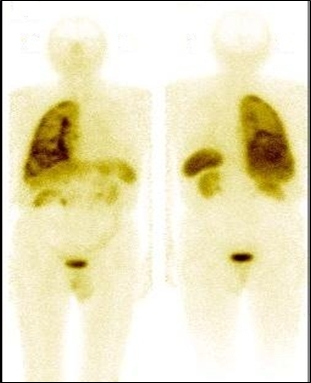

Se realizó la gammagrafía de cuerpo entero con 20 mCi (740 MBq) de octreotide marcado con 99mTc (fig. 2), obteniéndose imágenes a la 1, 4 y 24 horas post-inyección, incluyendo adquisiciones de tomografía por emisión (SPECT). La reconstrucción del estudio SPECT se llevó a cabo mediante algoritmo iterativo OSEM, con 8 subconjuntos y 4 iteraciones. El estudio demostró concentración patológica en todo el pulmón derecho; además, compromiso multifocal de hígado con incremento de su actividad en las vistas tardías.